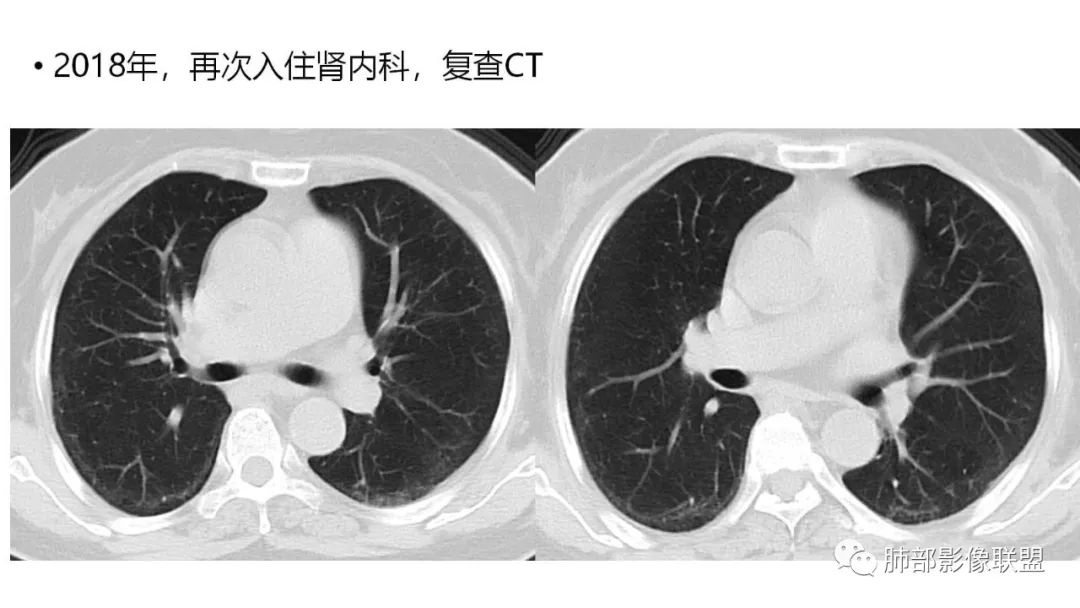

三、本例是一个误诊多年的病例,给我们很多启示:

1.多学科探讨的重要性:肾内科忽视肺部病变,后续需要呼吸、影像、病理共同探讨。

4.回到本例,左下肺病变两次好转,均未经过肿瘤治疗,第一次是支气管镜后,第二次是当其他病变都在进展的情况下,左下肺病变范围反而缩小趋于浅淡。